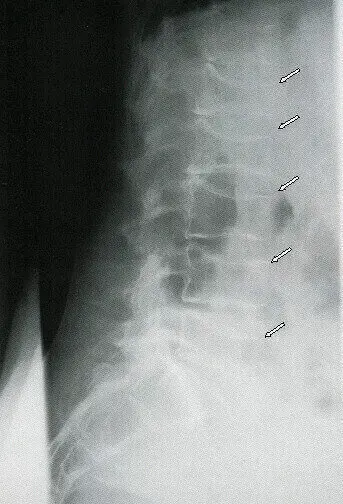

Остеопороз сопровождается повышенной ломкостью кости. Переломы (Рис.6) могут возникать без видимой причины, даже при минимальных нагрузках или неловких движениях. Примером могут служить снижение высоты позвонков – т.н. «платиспондилия» (см. рисунок ниже, №5)

![]() |

| Рис. 5. Множественные переломы тел позвонков на рентгенограмме. Компрессионные переломы указаны стрелками | Рис. 6. Перелом бедренной кости при остеопорозе (так называемый чрезвертельный, указан стрелками) |